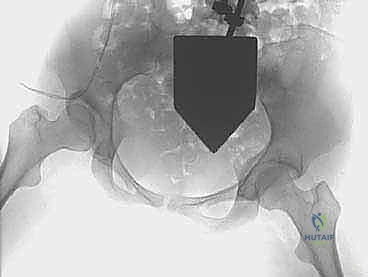

2. سلسلة قطع العظام (The 5 Osteotomies)

يكمن سر نجاح جراحة PAO في إجراء خمسة قطوع عظمية منفصلة حول الحُق، لتحريره بالكامل عن باقي الحوض، مع ترك العمود الخلفي سليماً كدعامة أساسية.